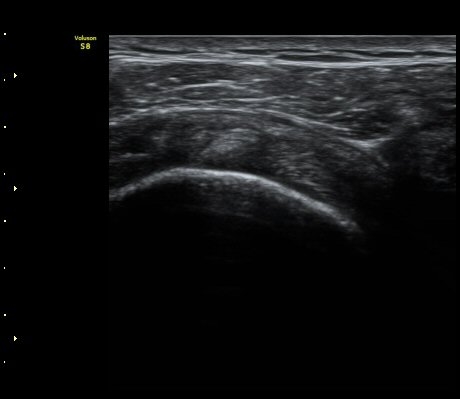

3°³¿ù ÈÄ ÃßÀû°Ë»ç

2049205267_a5fe3a8a_US181253111.jpg

2049205267_e81a53aa_US181338113.jpg